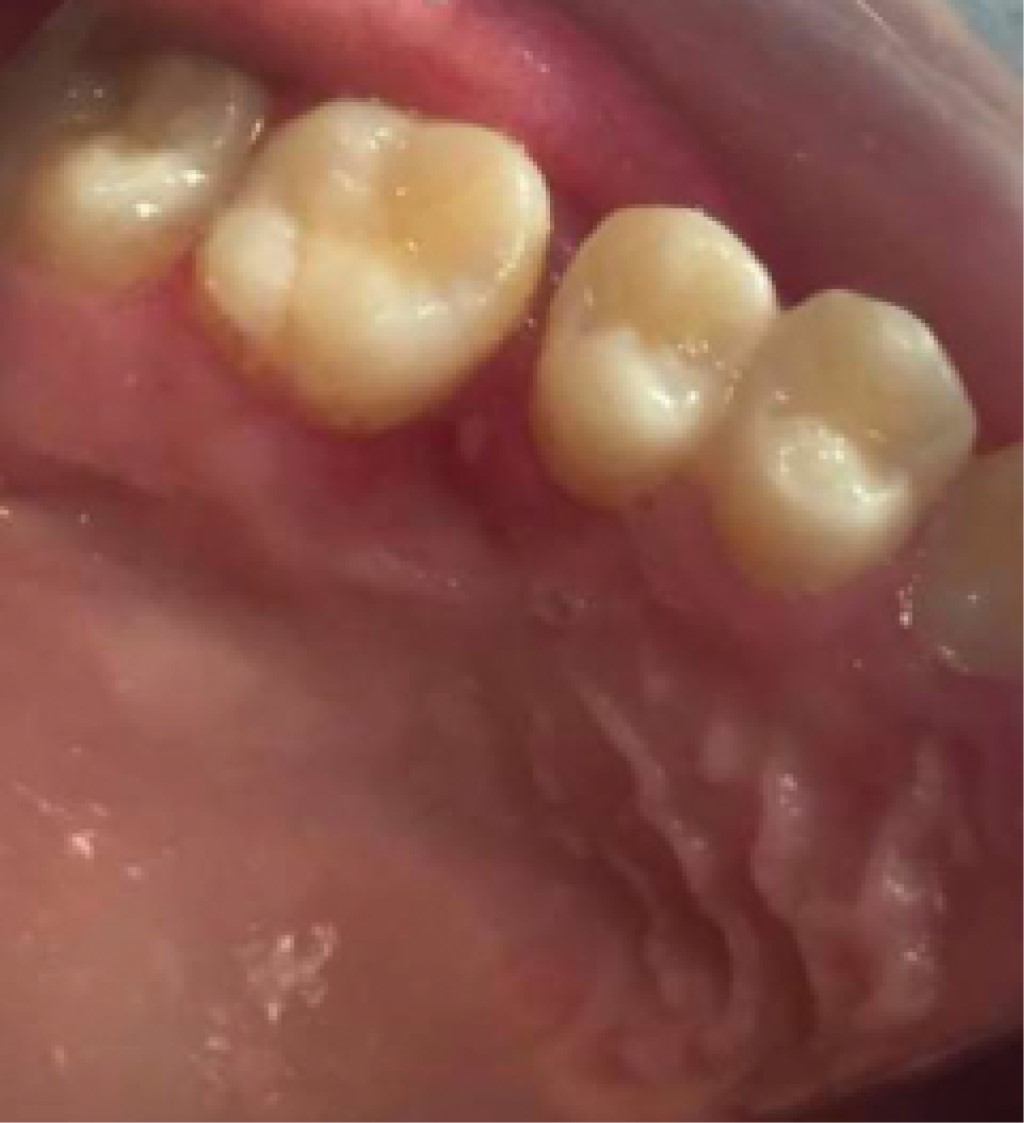

Solitary neurofibromas have been reported in the literature, but they are very rare cases. By definition they occur in patients who do not have Von Recklinghausen disease, which is inherited in an autosomal dominant manner; It occurs more frequently in men. It is a benign tumor that can appear solitary or multiple. Its appearance in the oral cavity is usually very rare, but its site of preference is the tongue, followed by the alveolar mucosa, palate, and gingival gingiva. They appear more frequently during the third decade of life, although cases from 10 months to 70 years of age are described. This report will present the clinical case of a 17-year-old female patient who came to the Centennial Dental Clinic for consultation presenting an elevated lesion covering part of the anatomical crowns in dental pieces in the left upper jaw and in the report. Neurofibroma was diagnosed from the Immunochemical-histological study, with S-100 expression. We consider the recognition of these intraoral growths of utmost importance in order to establish a true and truthful definitive diagnosis of the situation.

Figure 1

Figure 2

Figure 3

Figure 4

Figure 5

Figure 6

Figure 7